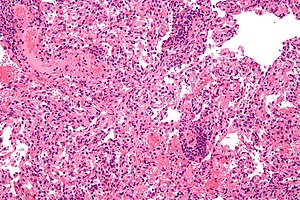

| Micrograph showing lung transplant rejection. Lung biopsy. H&E stain. | |

Developing with formation of cellular immunity, acute rejection occurs to some degree in all transplants, except between identical twins, unless immunosuppression is achieved (usually through drugs). Acute rejection begins as early as one week after transplant, the risk being highest in the first three months, though it can occur months to years later. Highly vascular tissues such as kidney or liver often host the earliest signs—particularly at endothelial cells lining blood vessels—though it eventually occurs in roughly 10 to 30% of liver transplants, and 10 to 20% of kidney transplants. A single episode of acute rejection can be recognized and promptly treated, usually preventing organ failure, but recurrent episodes lead to chronic rejection. It is believed that the process of acute rejection is mediated by the cell mediated pathway, specifically by mononuclear macrophages and T-lymphocytes. Histology of acute rejection is defined by dense lymphocytic cellular infiltrate as well as vasculitis of organ donor vessels.[citation needed]

Diagnosis of acute rejection relies on clinical data—patient signs and symptoms but also calls on laboratory data such as blood or even tissue biopsy. The laboratory pathologist generally seeks three main histological signs: (1) infiltrating T cells, perhaps accompanied by infiltrating eosinophils, plasma cells, and neutrophils, particularly in telltale ratios, (2) structural compromise of tissue anatomy, varying by tissue type transplanted, and (3) injury to blood vessels. Tissue biopsy is restricted, however, by sampling limitations and risks/complications of the invasive procedure.[26][27][28] Cellular magnetic resonance imaging (MRI) of immune cells radiolabeled in vivo might—similarly to Gene Expression Profiling (GEP)—offer noninvasive testing.[29][30]